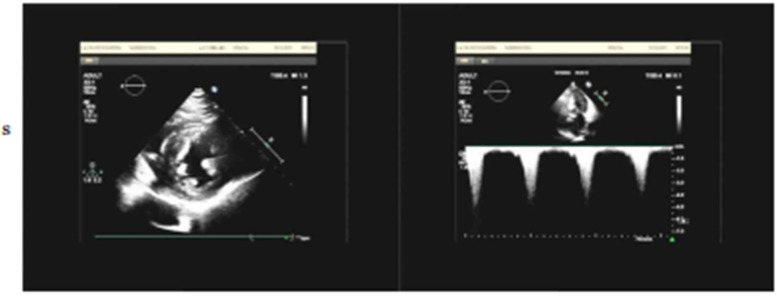

Case presentation: We report a case of a 68-year-old female diagnosed with severe HOCM who experienced transient hypertension (165/105 mmHg) and myalgia four weeks after mavacamten initiation. Despite a significant reduction in LVOT obstruction (from 64 mmHg-18 mmHg) and an increase in LVEF to 78%, the patient exhibited a transient hypertensive response that resolved spontaneously within two weeks without intervention. Myalgia was present without corresponding elevations in serum creatine kinase.